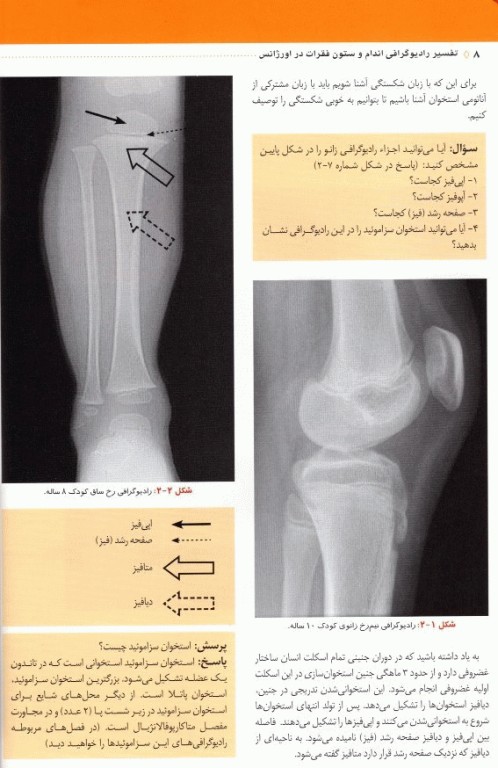

کتاب تفسیر رادیوگرافی اندام و ستون فقرات در اورژانس تالیف دکتر سعیدرضا مهرپرور، دکتر امیر محلیشا کاظمی و دکتر محمدجواد دهقانی توسط انتشارات طبیب و تیمورزاده به مرحله چاپ و تولید رسیده است. با مطالعه این اطلس رادیولوژی، کلیه دانشجویان و پزشکان به آسانی می‌توانند در مواجهه با آسیب‌های اندام و ستون فقرات در اورژانس، با تشخیص صحیح، رادیوگرافی مرتبط با آن را درخواست کنند و بیمار نیز در معرض اشعه زیان بار ایکس قرار نگیرد. همچنین خوانندگان با مطالعه این اثر قادر خواهند بود یک رادیولوژی ساده اندام و ستون فقرات را به درستی تفسیر کنند، بنابراین درمان بیمارشان را با اعتماد به نفس بیشتری انجام خواهند داد. خواندن این کتاب به تمام دانشجویان پزشکی، پزشکان عمومی، دستیاران ارتوپدی، دستیاران و متخصصین طب اورژانس و تمام عزیزانی که به نحوی در اورژانس فعالیت می‌کنند و همچنین تمام متخصصینی که خواندن رادیوگرافی ساده برای آنها اهمیت دارد(مانند متخصصین داخلی، روماتولوژی، انکولوژی، پاتولوژی، رادیوتراپی و...) توصیه می‌شود.